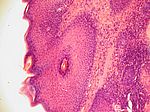

Keratoakanthom, HE